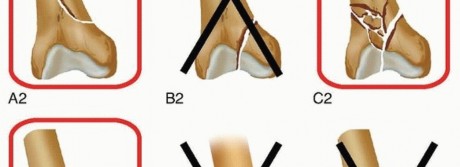

### FIG 5 • Muller's AO classification system of distal femoral fractures,16 with fracture patterns amenable to retrograde femoral nailing highlighted.

### FIG 5 • Muller's AO classification system of distal femoral fractures,16 with fracture patterns amenable to retrograde femoral nailing highlighted.  ---

FIG 6 • A. Diagram of lateral aspect of distal femur, with potential sites for intra-articular screw fixation out of the path of the retrograde femoral nail identified. B. Diagram of distal femur end on, with potential sites for intra-articular screw fixation out of the path of the retrograde femoral nail identified. C. Intraoperative lateral radiograph of a supracondylar, intracondylar (C1) distal femur fracture with intra-articular screw fixation and retrograde nail in place. Consideration for retrograde femoral nailing can be given to simple transverse articular fracture patterns (C-1 and C-2 subgroups). This should be performed with an open medial or lateral parapatellar approach to the knee in lieu of a percutaneous approach. Articular reduction must first be obtained and then maintained with bicortical screw fixation placed outside of the planned path for the retrograde nail ( FIG 6). Partial articular fractures (all B subgroups) and complex articular fractures (C-3 subgroups) should not be considered for retrograde femoral nailing. Patients with osteoporotic distal fractures may be best treated with some of the newer fixed-angle plate devices, owing to concerns of distal interlocking screw purchase. Alternatively, nails designed with multiaxial screws or the use of supplemental blocking screws may help with augmenting fixation. ## Contraindications Preoperative knee stiffness preventing 40 to 60 degrees of flexion Active knee sepsis Grossly contaminated soft tissue wounds about the knee remain a contraindication but recent literature has shown that retrograde nailing of open fractures does not increase the incidence of postoperative knee sepsis. 22 Skeletally immature patients ## Preoperative Planning AP and lateral radiographs are used to measure the diameter of the femoral canal isthmus and thus determine the approximate nail diameter. Most intramedullary nail systems come in diameters ranging from 10 to 13 mm.*

FIG 6 • A. Diagram of lateral aspect of distal femur, with potential sites for intra-articular screw fixation out of the path of the retrograde femoral nail identified. B. Diagram of distal femur end on, with potential sites for intra-articular screw fixation out of the path of the retrograde femoral nail identified. C. Intraoperative lateral radiograph of a supracondylar, intracondylar (C1) distal femur fracture with intra-articular screw fixation and retrograde nail in place. Consideration for retrograde femoral nailing can be given to simple transverse articular fracture patterns (C-1 and C-2 subgroups). This should be performed with an open medial or lateral parapatellar approach to the knee in lieu of a percutaneous approach. Articular reduction must first be obtained and then maintained with bicortical screw fixation placed outside of the planned path for the retrograde nail ( FIG 6). Partial articular fractures (all B subgroups) and complex articular fractures (C-3 subgroups) should not be considered for retrograde femoral nailing. Patients with osteoporotic distal fractures may be best treated with some of the newer fixed-angle plate devices, owing to concerns of distal interlocking screw purchase. Alternatively, nails designed with multiaxial screws or the use of supplemental blocking screws may help with augmenting fixation. ## Contraindications Preoperative knee stiffness preventing 40 to 60 degrees of flexion Active knee sepsis Grossly contaminated soft tissue wounds about the knee remain a contraindication but recent literature has shown that retrograde nailing of open fractures does not increase the incidence of postoperative knee sepsis. 22 Skeletally immature patients ## Preoperative Planning AP and lateral radiographs are used to measure the diameter of the femoral canal isthmus and thus determine the approximate nail diameter. Most intramedullary nail systems come in diameters ranging from 10 to 13 mm.*